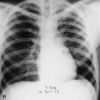

ÍÒ¡Òâͧâä¡ÒÌâä»Í´ : ÍÒ¡Ò÷ѹ㴠ä¢éÊÙ§ ˹ÒÇÊÑè¹ »Ç´ËÑÇÃØ¹áç ÍÒ¡ÒÃäÍà¡Ô´¢Öé¹ã¹ 24 ªÑèÇâÁ§ àÊÁËе͹ááà˹ÕÂÇãÊáÅéÇ¡ÅÒÂà»ç¹ÊÕʹÔÁËÃ×Íá´§Ê´ ÁÑ¡äÁèÁÕ»×é¹á¼Å㹻ʹ ¶éÒäÁèÃÑ¡ÉÒ : µÒÂÀÒÂã¹ 48 ªÑèÇâÁ§